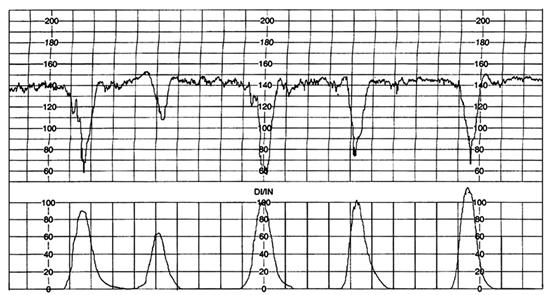

Fig. nr. 296 Bradicardie in timpul hipertoniei si hiperkineziei uterine

Schimbarea ritmului cardiac de baza se defineste prin modificarea RCFB cu 20-40 bpm .

Fig . nr. 297 Schimbarea RCFB